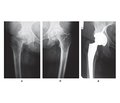

Коломаченко В.І. (1, 2), Одинець І.Ю. (1), Гавриков О.Є. (1, 2), Купін В.І. (2)

(1) - Харківський національний медичний університет, м. Харків, Україна

(2) - Харківська обласна клінічна травматологічна лікарня, м. Харків, Україна